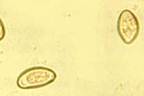

Яйца Opistorchus felineus

Яйцо Opistorchus viverrini

Этиология. Возбудителями описторхоза являются два вида трематод семейства 0pisthorchidae: Opisthorchis felineus и Opisthorchis viverrini. О. felineus (синонимы: двуустка кошачья, двуустка сибирская) имеет плоское тело длиной 4—13 мм и шириной 1—3,5 мм. Ротовая присоска — у переднего конца тела, брюшная - на границе первой и второй четвертей тела. Яйца бледно-желтой окраски, с нежной двухконтурной оболочкой, с крышечкой на одном полюсе и утолщением скорлупы на противоположном конце; их размер 0,010—0,019 х 023—0,034 мм. В стадии половой зрелости О. felineus паразитирует во внутри- и внепеченочных желчных протоках, в желчном пузыре, протоках поджелудочной железы человека, кошки, собаки, лисицы, песца и некоторых других плотоядных животных. Промежуточным хозяином гельминта является пресноводный жаберный моллюск Bithynia leachi. Дополнительные хозяева —рыбы семейства карповых: язь, елец, чебак, плотва европейская, вобла, линь, красноперка, сазан, лещ, густера, подуст, жерех, уклея. О. viverrini весьма близок к О. felineus. Длина гельминта 5,4—10,2 мм, ширина 0,8—1,9 мм. Пищевод гельминта в 3 раза длиннее его глотки. В стадии половой зрелости паразитирует в желчных протоках, в желчном пузыре и протоках поджелудочной железы человека, кошки, плотоядного зверя виверры, собаки. Промежуточные хозяева гельминта — моллюски рода Bithynia, дополнительные хозяева — пресноводные карповые рыбы.